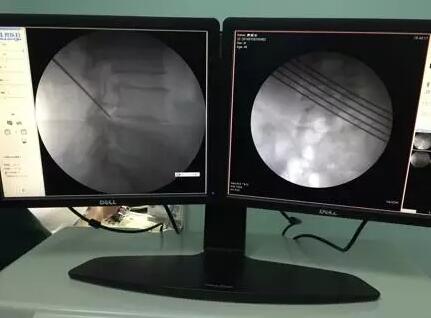

▲椎間孔鏡術(shù)中穿刺定位